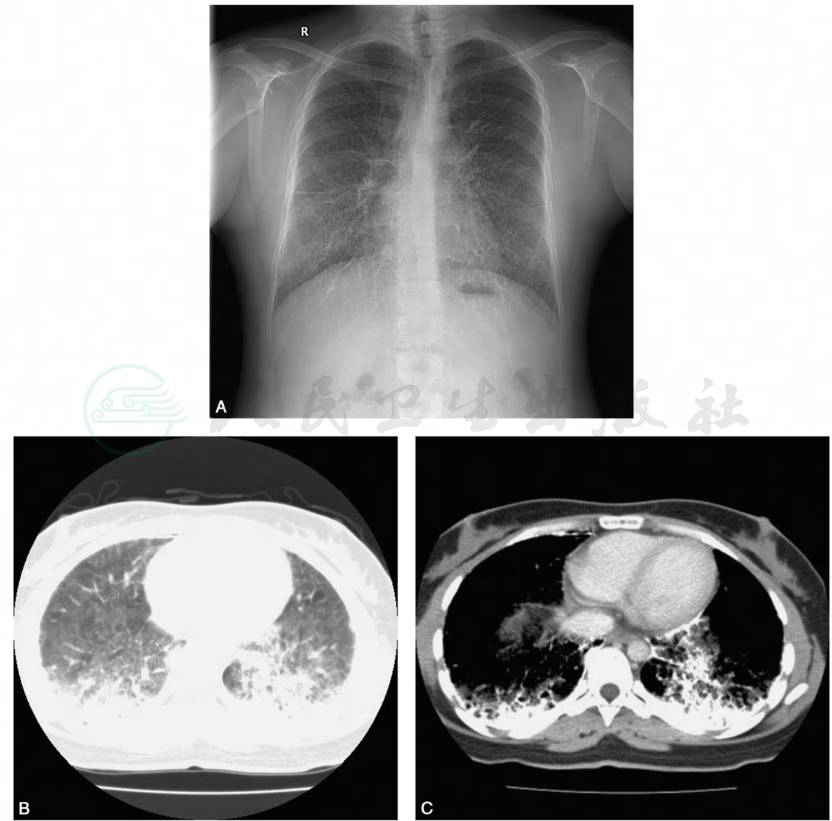

(一)X线检查

X线是发现及提示本病最基本的手段,表现为两肺弥漫性分布的、边缘锐利、大小基本一致、呈钙化密度的沙砂样微结节,肺下野多于肺上野。随着病情进展,两肺结节影密集,可出现病灶聚集融合,心膈模糊,呈“沙暴”或“雪暴”样改变即典型的“暴风沙症”。病情较重者,呈“白肺样”表现,肺组织、纵隔及肋骨完全被掩盖。在侧胸壁与肺外缘之间可见狭长透亮带,称为“黑胸膜线”。

(二)CT检查

胸部HRCT主要表现包括:①双肺透亮度降低,呈磨砂玻璃样改变,见于90%的患者;②部分呈肺间质纤维化的表现;③弥漫性分布的微小结节,密度较高,可呈特征性的钙化影;④胸膜下排列成行的直径5~10mm薄壁小气囊形成黑胸膜线;⑤纵隔窗显示肺野内不规则点状、条状致密影,胸膜下可融合成片形成“火焰征”和“白描征”(图2)。

图2肺泡微结石症的胸部影像学表现

A.X线片:双肺弥漫性分布的细小沙砾状结节影,中下肺野为主;B.CT:双肺透亮度降低,呈磨砂玻璃样改变,弥漫性分布的微小结节,密度较高;C.纵隔窗显示肺野内不规则点状、条状致密影,胸膜下可融合成片形成“火焰征”和“白描征”。